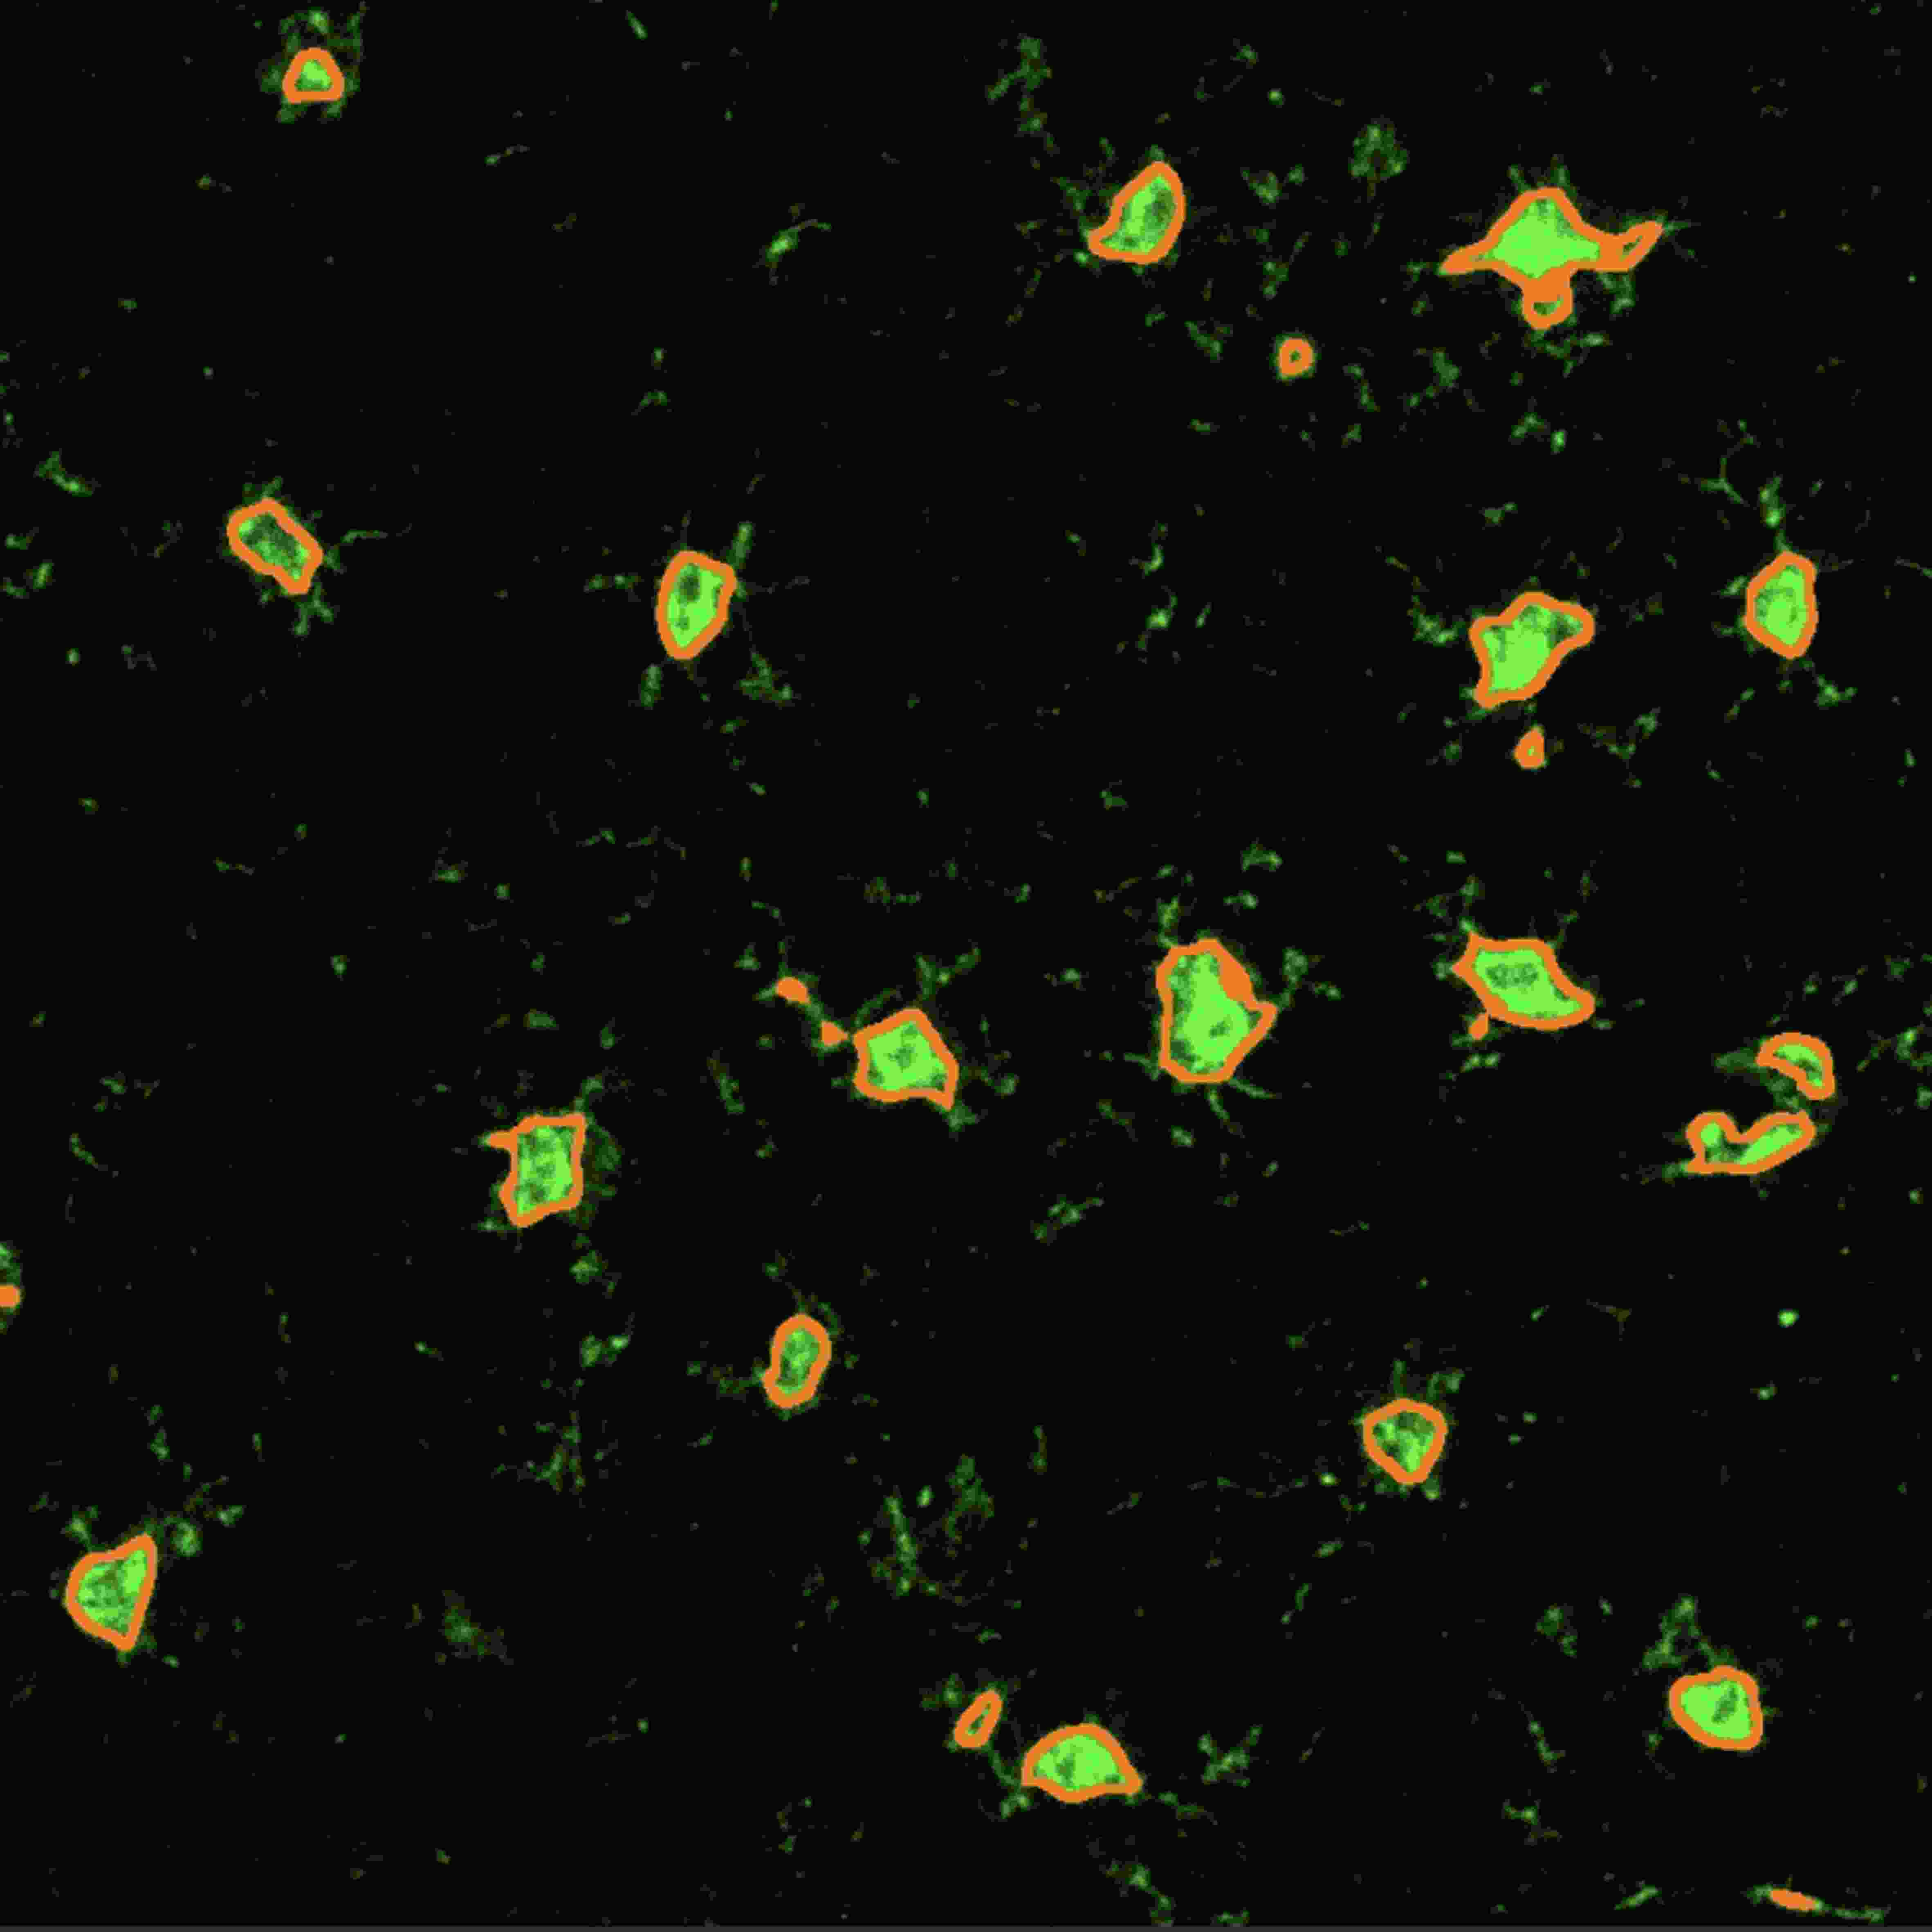

采用TG细胞核识别算法,对组织切片中单细胞进行统计分析,进一步通过细胞质算法获得panel种每个指标阳性阈值,以分析不同指标之间的共表达情况,鉴定不同细胞亚群。

分析内容:总细胞计数、阳性细胞计数、阳性细胞平均强度、阳性细胞百分比等数据